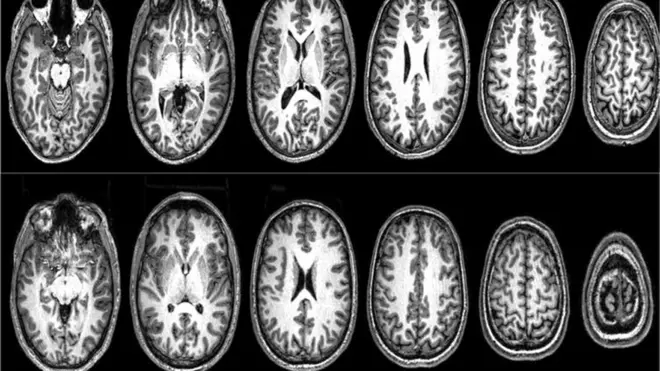

Yuste es uno de los científicos decididos a regular el uso futuro de las neurotecnologías: herramientas que hoy se desarrollan para mapear y modificar la actividad del cerebro humano.

Yuste fue uno de los primeros asesores del proyecto "Brain" ("cerebro", en inglés) lanzado en 2013 por el entonces presidente estadounidense, Barack Obama, con el fin de impulsar y financiar neurotecnologías capaces de "mapear" el cerebro.

"Toda esa complejidad de neuronas se está disparando electrónicamente y a través de procesos que no entendemos. De allí surge la visión, las sensaciones, el comportamiento, las ideas, la memoria, las emociones, la conciencia, la mente, todo lo que somos. Por eso es tan importante contar con neurotecnologías capaces de mapearlas".

Las neurotecnologías utilizan técnicas ópticas, electrónicas, magnéticas y nanotecnologías para comprender estos procesos y a futuro, "leer y escribir" la actividad cerebral.